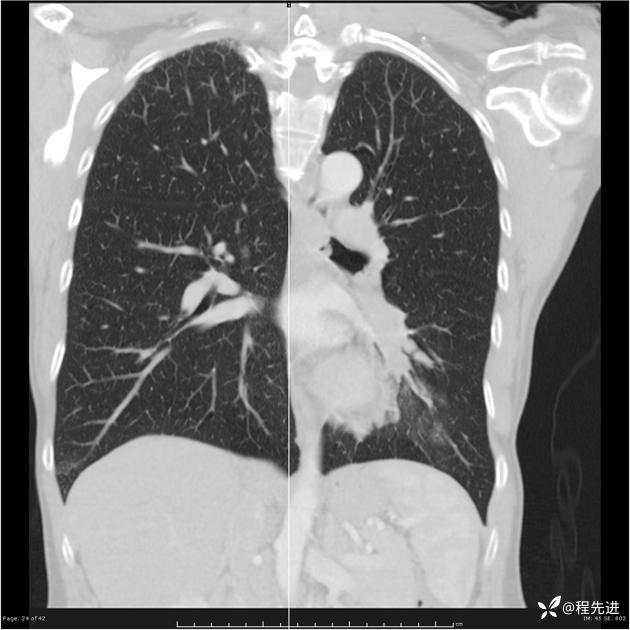

病例女,53岁,气管、左主支气管、下叶支气管内结节,乳头状瘤?期待你的精彩解读

女,53岁

乳头状瘤?